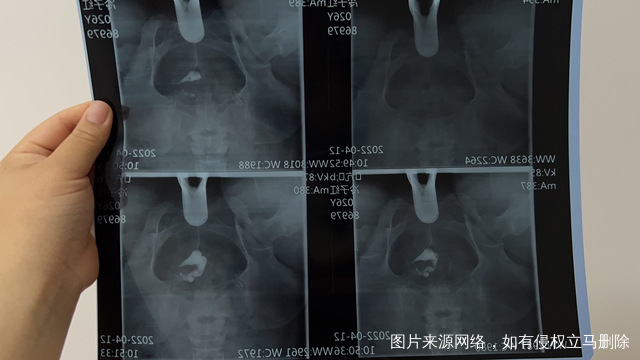

我去检查了输卵管 一边积水 一边堵了 我想知道做试管用不用先把积水取出来

这个手术不是非得要马上做,需要根据你的年龄、生育计划等来综合评估并权衡利弊后再决定是否需要手术以及什么时候做。如果是做试管通常为了避免输卵管积液及炎症因子逆流至宫腔影响胚胎着床等,会行输卵管结扎等手术,这个手术通常在移植前完成